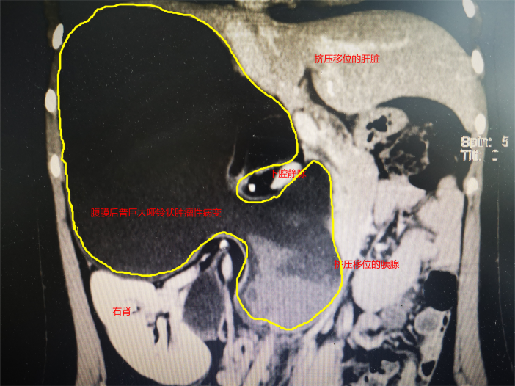

腹膜后肿瘤性疾病手术素来都是腹腔手术中的“大手术”,变异的解剖结构、困难暴露的手术视野以及复杂的肿瘤性质使手术难度居高不下,令许多普外科医师望而却步。